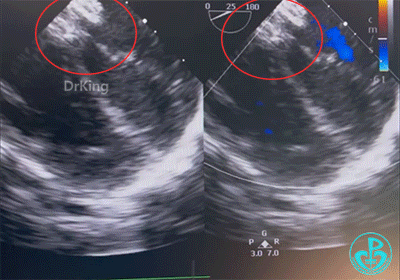

展开左右盘面

先后展开左右盘面并前推钢缆辅助成型,而后确认封堵器位置是否合适并评估血流。

经评估,封堵器形态大小合适,彩超提示无血液分流。